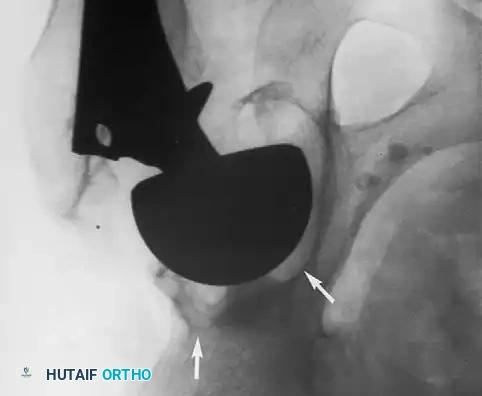

Associated Surgical & Radiographic Imaging